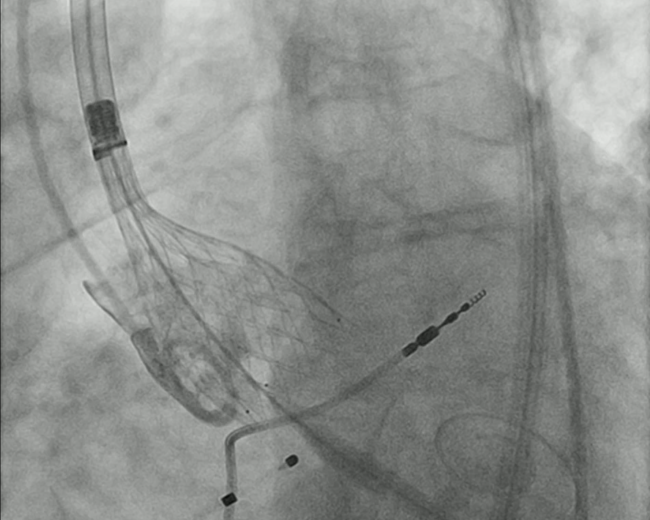

In the present procedural steps for an SEV (Video 1), namely the Evolut series (Medtronic), the guidewire is withdrawn up to the terminal part of the nosecone of the delivery catheter to allow coaxiality, prevent cantering, and maintain a center trajectory of the deploying valve (Video 2). This also prevents inadvertent ventricular ectopics, which could hamper precise positioning. After valve deployment, the wire is repositioned in the mid-LV cavity, the delivery catheter and in-line sheath are removed, and the Sentrant sheath (Medtronic) is repositioned. Next, a pigtail catheter is placed in the LV for transvalvular gradients, which is removed on a J-wire.

We propose that, after the valve is deployed satisfactorily, the delivery catheter be removed with the stiff wire, keeping it in the upper descending aorta (not the LV cavity) (Video 3). The stiff wire would then be exchanged with a Hi-Torque Supra Core (Abbott) to prevent the coil of the Safari (or another guidewire) from interacting with the distal aorta and the iliac and femoral arteries. The Perclose ProGlide would be sequentially tightened on this wire to prevent bleeding.

This "early" removal of the guidewire is done only after valve stability, anchoring, and absence of infolding have been established. Coronary patency, aortic annular integrity, and absence of evidence of annular rupture also need to be confirmed. Mild to moderate paravalvular leak is not considered as a contraindication to this early removal and thus must be checked by echocardiography after the delivery catheter and guidewire have been brought to the descending aorta.